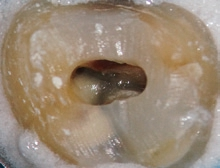

Dr. Brüsehaber: Ich beginne die Trepanation der Pulpakammer sehr gern mit einer Diamantkugel (z. B. 6801L, Komet) (Abb.1). Wenn ich damit das Pulpencavum direkt eröffnen kann, gilt es, im nächsten Behandlungsschritt die Hartsubstanzüberhänge abzutragen, um einen „straight line access“ zu den Wurzelkanälen zu schaffen (Abb. 2 und 3). Ein geradliniger Zugang ist essentiell für alle weiteren Behandlungsschritte. Mit ausreichender Erfahrung und unter Verwendung eines Operationsmikroskops ist es möglich, das Wurzelkanalsystem auch über eine sehr kleine Zugangsöffnung zu behandeln.